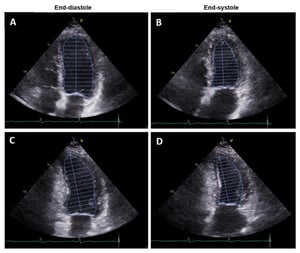

El strain del ventrículo izquierdo surge como una herramienta complementaria que permite evaluar la deformación del miocardio durante el ciclo cardíaco. Mediante técnicas de ecocardiografía con speckle tracking, es posible analizar el comportamiento de las fibras miocárdicas con mayor sensibilidad, detectando alteraciones funcionales antes de que se manifiesten cambios en la FEVI.

El strain longitudinal global (GLS) mide el acortamiento de las fibras miocárdicas en el eje longitudinal, desde el ápex hacia la base. Este parámetro refleja principalmente la función de las fibras subendocárdicas, que son las más susceptibles al daño precoz.